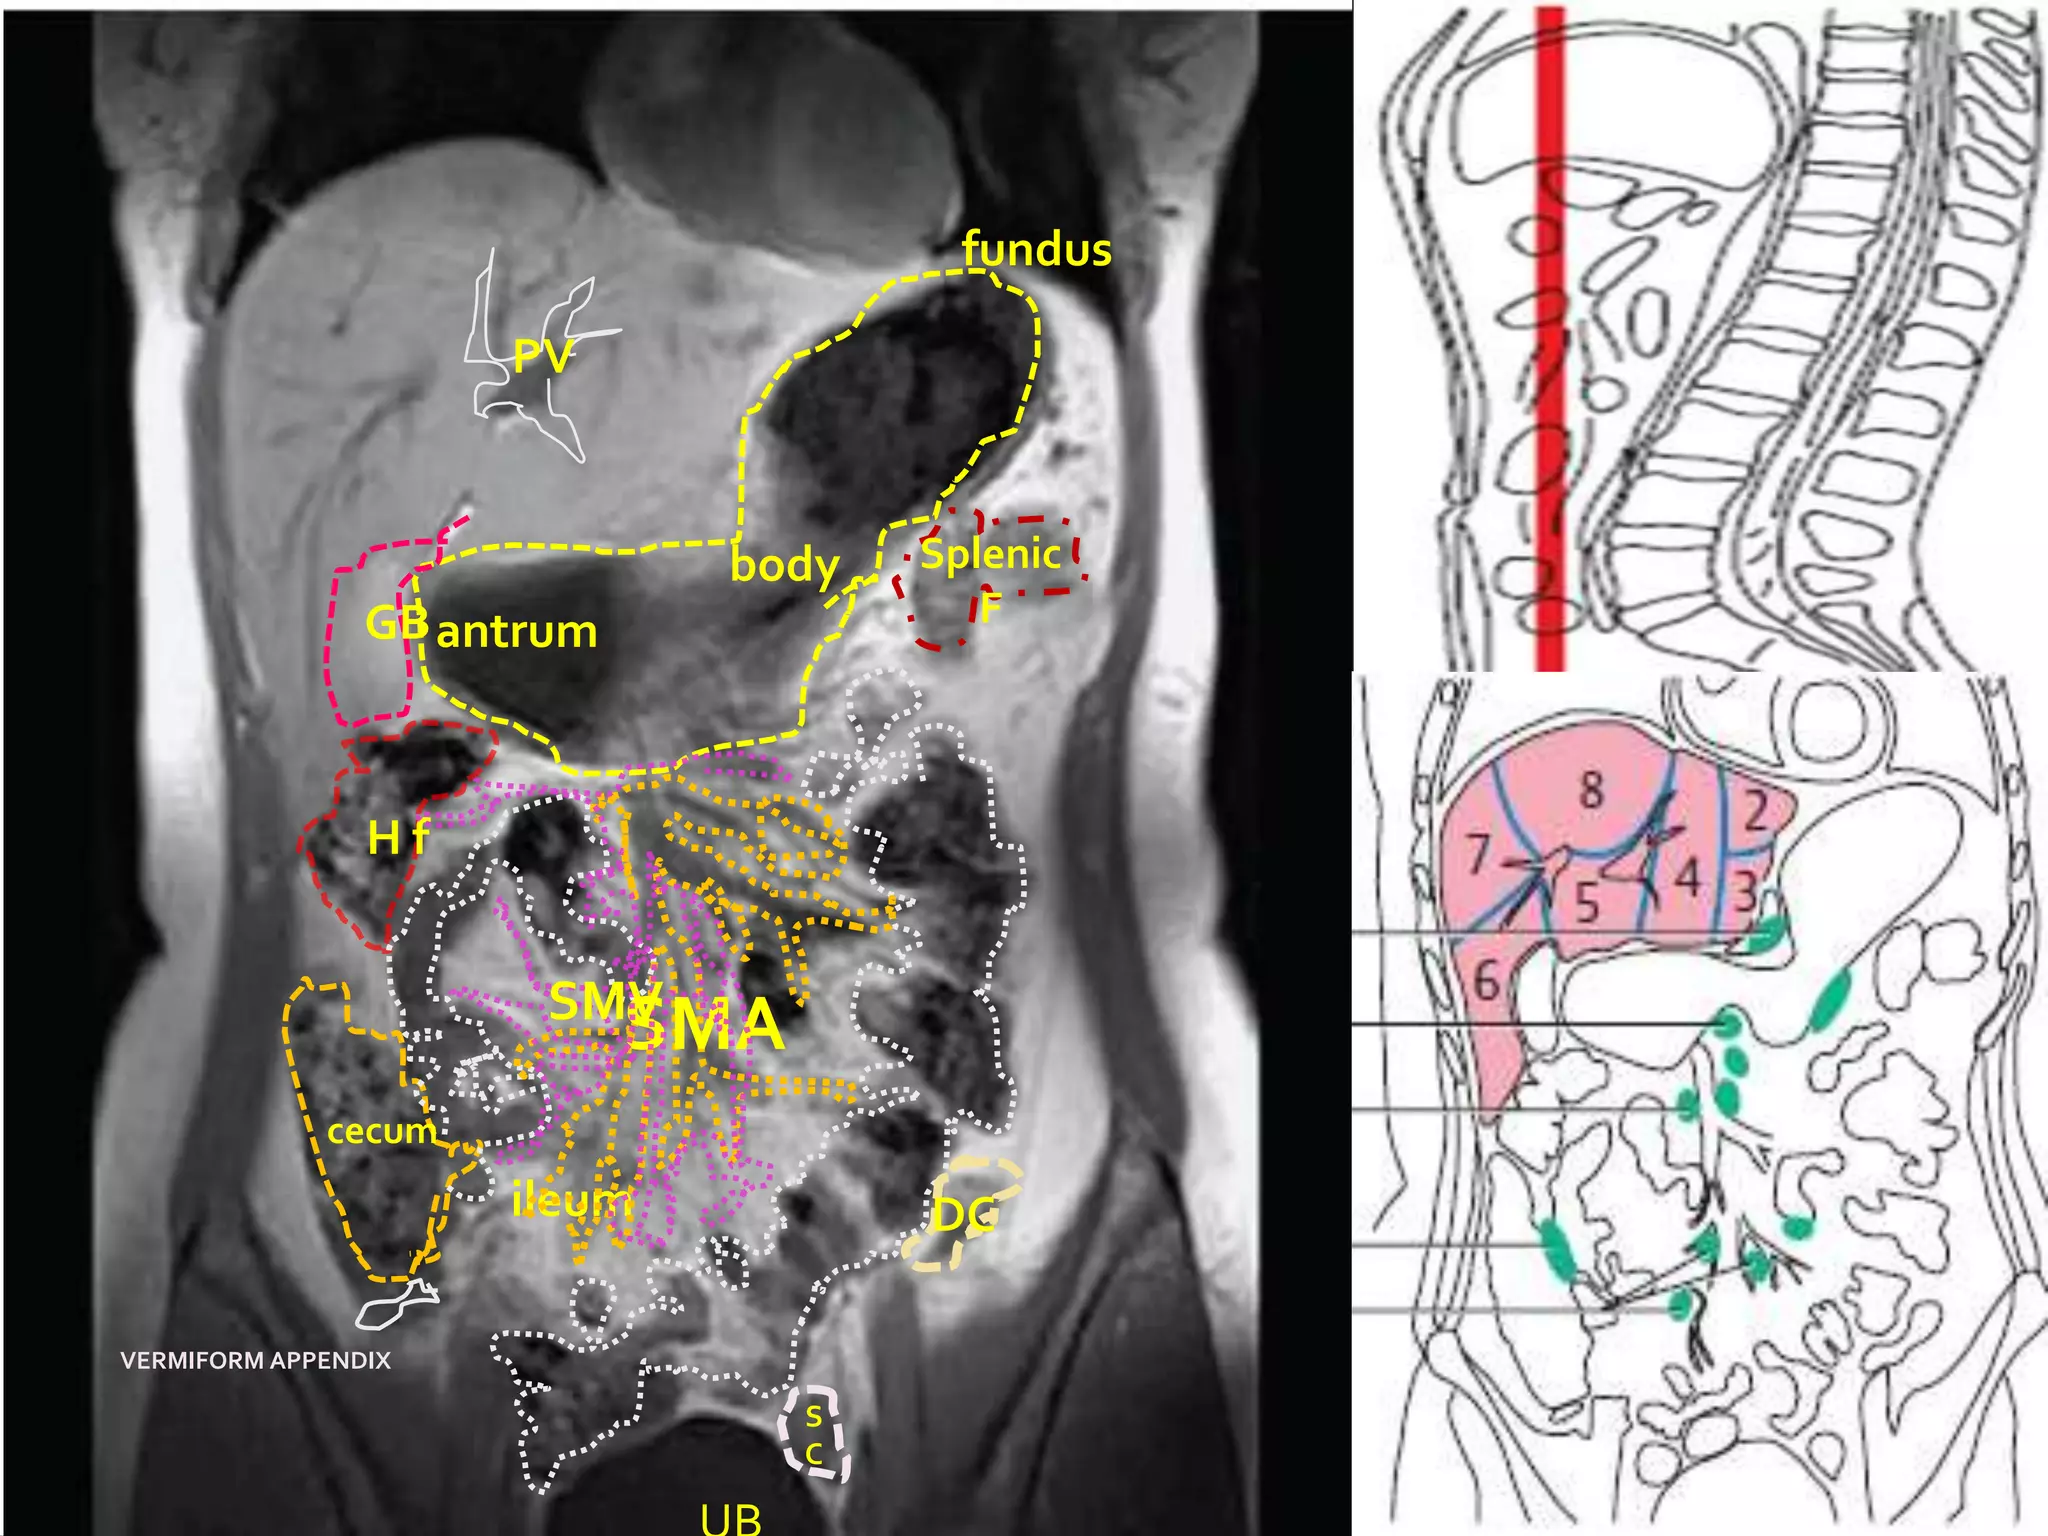

fundus

PV

body     Splenic

GB antrum                F

Hf

SMV

SMA

cecum

ileum            DC

VERMIFORM APPENDIX

S

C